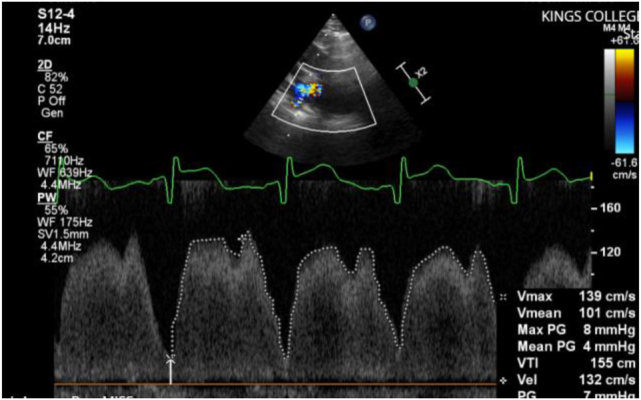

Case presentation: A preterm female infant born at 23+5 weeks gestation had numerous complications related to extreme prematurity, including BPD. She was diagnosed with PVS on echocardiogram after experiencing recurrent respiratory deteriorations and pulmonary hypertensive crises. Initial management involved transcutaneous balloon dilatation. A serial echocardiographic programme was implemented, with weekly monitoring of PVS. She suffered multiple respiratory deteriorations secondary to recurrence of PVS, necessitating repeat cardiac catheterisations and transcatheter stenting. Systemic macrolide therapy with sirolimus was used as adjunctive therapy.